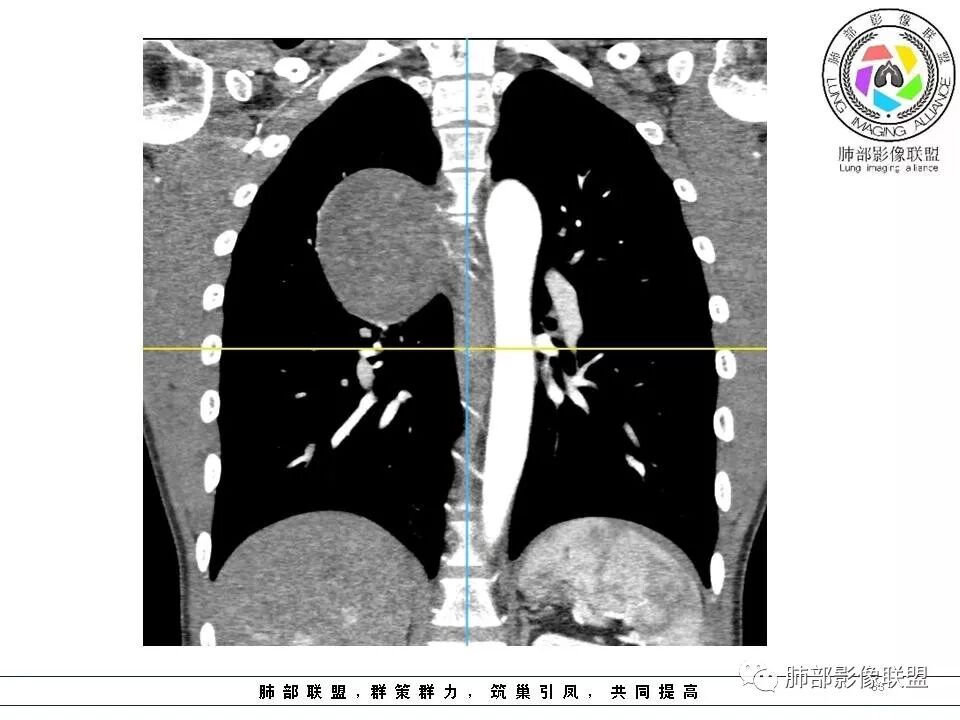

右后纵膈脊柱旁软组织占位,形态规则类圆,边缘光整,肺组织受压,胸膜尾,肋间动脉供血。中度不均匀延迟强化。

后纵隔脊柱旁占位性病变,疾病谱有神经鞘瘤,sft,节细胞瘤,髓外造血。此例有胸膜尾征,蛇纹征 ,延迟强化。考虑胸膜孤立性纤维瘤。看到有供血动脉,但不知道是哪里的血管。

后纵隔类圆形新生物,边缘光滑,胸膜尾征明显,贴近脊柱,蛇纹,血供丰富,考虑后纵隔软组织肿瘤,具体类型看不出来,鉴别神经鞘瘤。

右后纵膈脊柱旁软组织占位,边界清晰,光整,肺组织受压。胸膜被掀起,肋间动脉供血,中度不均匀延迟强化。考虑神经鞘瘤,不除外纤维瘤

右后纵膈脊柱旁软组织影,与纵隔结构分界不清,形态规则类圆,边缘光整,肺组织受压,胸膜尾,肋间动脉供血。肺动脉推移,中度不均匀延迟强化。考虑神经来源,神经鞘瘤,神经纤维瘤二者不易鉴别。

青年男性,间断胸痛;右侧脊柱旁可见一类圆形软组织密度影,密度欠均匀,增强扫描呈轻中度持续强化,邻近肺组织及肺动脉推移,可见肋间动脉供血,部分胸膜下脂肪可见,部分层面似见与右侧椎间孔相连。考虑后纵隔神经源性肿瘤。

后纵隔脊柱旁占位性病变,有胸膜尾征,胸膜下脂肪可见,蛇纹征,明显强化。考虑孤立性纤维瘤。

边缘光滑,宽基底与胸壁相连,跨叶裂,叶裂稍前推,血管、支气管前移。

浅分叶

外上侧少量胸水

肋间动脉供血,强化尚均匀,逐步强化

1.右上胸内脊柱旁类圆形肿块,质地似乎比较坚实,密度稍显不均,但未显示明确的坏死。

如此密度形态的病灶位于肺边缘首先应当想到孤立性纤维瘤,可相邻胸膜未见明显的异常强化和胸膜方向延伸。

2.肋间动脉病供血也提示肿块来自后纵隔?